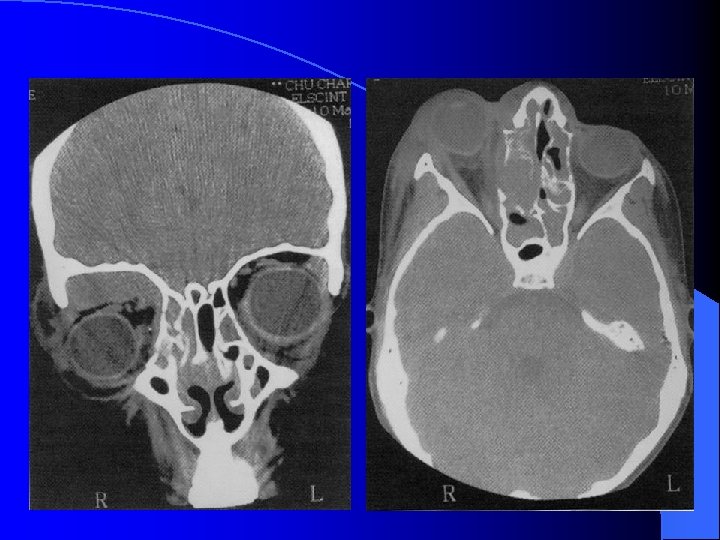

Ethmoïdite aiguë suppurée droite

Forme extériorisée = TDM

MALADIES INFECTIEUSES RHINO SINUSIENNES ETHMOIDITE AIGUË IMAGERIE • Radiographie standard • Echo doppler couleur (opérateur dépendant) • TDM sans et avec injection siège, stade collecté, analyse orbitaire fine